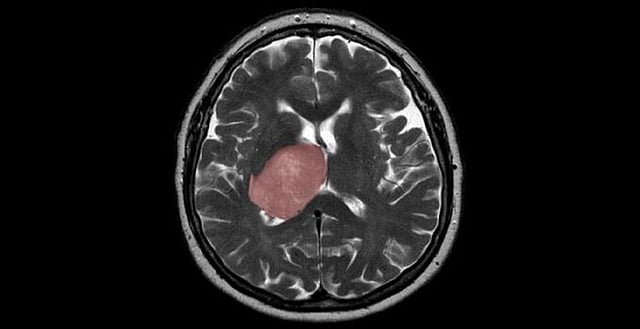

If you eat undercooked meat then you may need to stop it, as researchers have found a link between Toxoplasma gondii (T. gondii) infection and the risk of glioma, a rare type of brain cancer, in adults.

T. gondii is a common parasite that is most commonly acquired from undercooked meat and may lead to the formation of cysts in the brain.

The study, published in the International Journal of Cancer, suggests that people who have glioma are more likely to have antibodies to T. gondii (indicating that they have had a previous infection) than a similar group that is cancer-free.

These results suggest that reducing exposure to this common food-borne pathogen could provide a modifiable risk factor for highly aggressive brain tumors in adults.

Although glioma is a relatively rare disease, it is a highly fatal cancer. Globally in 2018, there were an estimated 300,000 incident cases and 241,000 deaths due to brain and other nervous system cancers, the researchers said.

The majority (80 percent) of malignant brain tumors are gliomas, for which the estimated five-year relative survival rate is a stark 5 percent, they added.